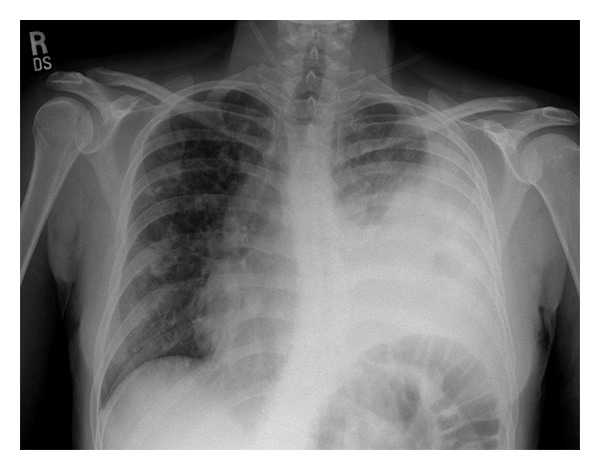

Input 3: What is seen in the X-ray and what should be done? ![]()